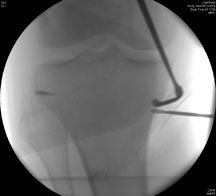

This picture on the left shows the fixation with an anchor on the side to put his ligaments back on again. As part of the osteotomy you can see the drill in position on the inner side of the leg, and that is aiming almost at the fibula. The next image on the right shows the chisel going in under X-ray guidance – the wire is the drill bit and then the slightly flat looking thing is the chisel.